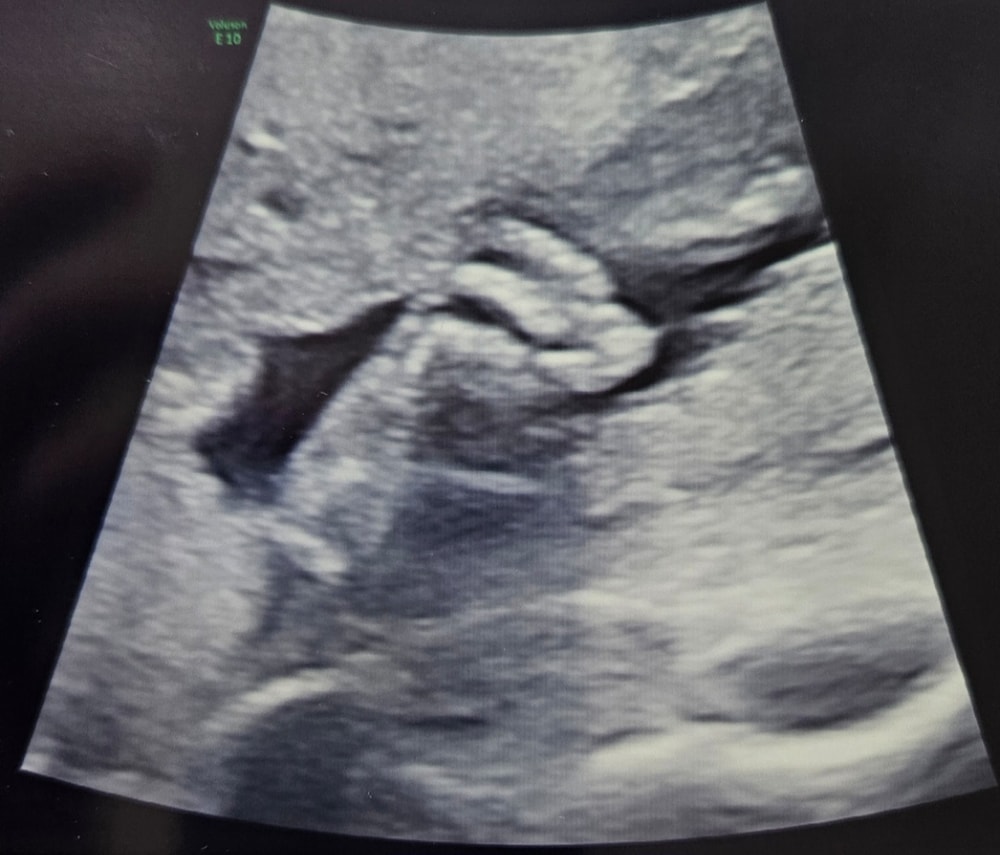

Наши будни, наши неделькиСходила на свое день рождения порадовала себя 3D фоточками. Сын никак не хотел фотографироваться прятался всячески! Ногу показал и то хорошо) сыночек мой любимый мы очень сильно любим и ждём🥰

Стопа 3,5 см) вес 600гр 22н2д